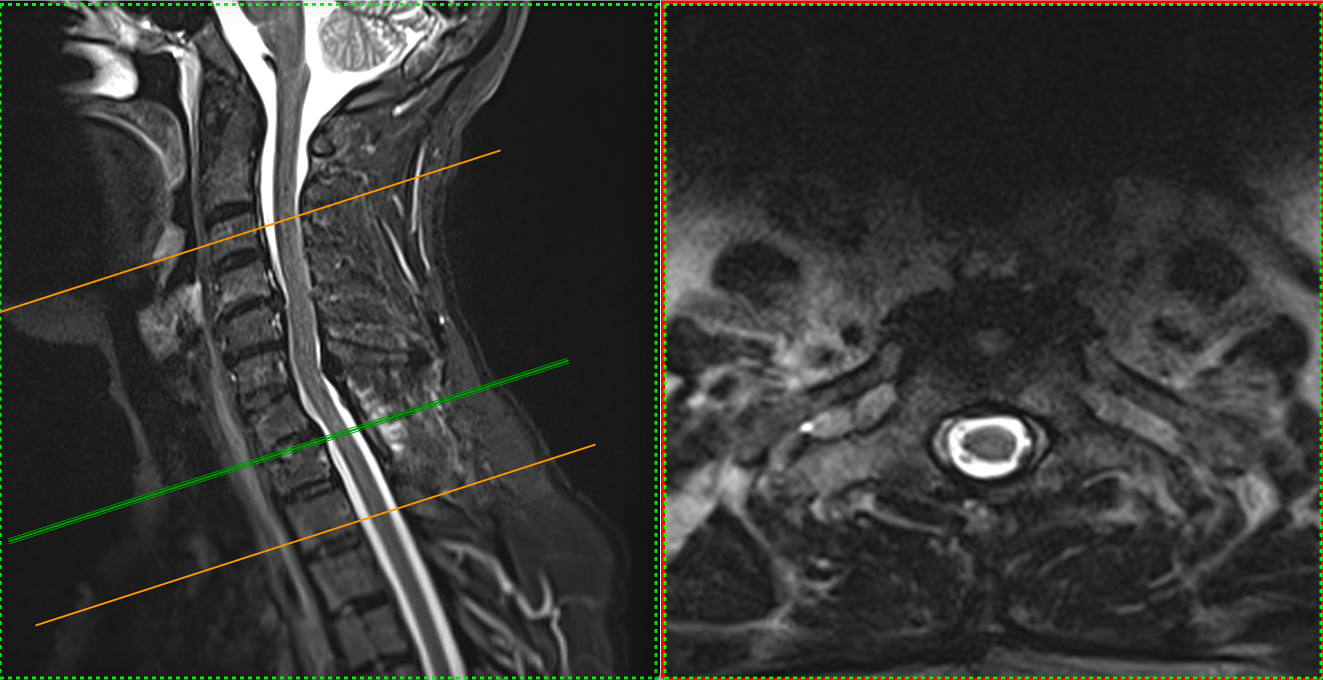

Investigația RMN spinal a evidențiat o formațiune intradurală extramedulară situată la nivel C7–T1, pe partea stângă.

Tumora prezenta caracteristici imagistice sugestive pentru un meningiom: leziune bine delimitată, cu captare omogenă de contrast, cu inserție pe meninge și efect de masă asupra măduvei.

Deși dimensiunea nu era foarte mare, localizarea era critică. La acest nivel, fibrele nervoase care controlează mișcările membrului superior sunt organizate compact, iar orice compresiune — chiar moderată — poate duce la deficit motor progresiv.

Măduva apărea deviată și comprimată, cu dispariția spațiului lichidian din jur — semn clar că structurile nervoase nu mai aveau spațiul necesar funcționării normale.

RMN-ul de control postoperator a evidențiat rezecția completă a formațiunii tumorale.

Măduva apare decomprimată, reexpansionată, cu refacerea spațiului lichidian perimedular — un indicator imagistic esențial al succesului chirurgical.